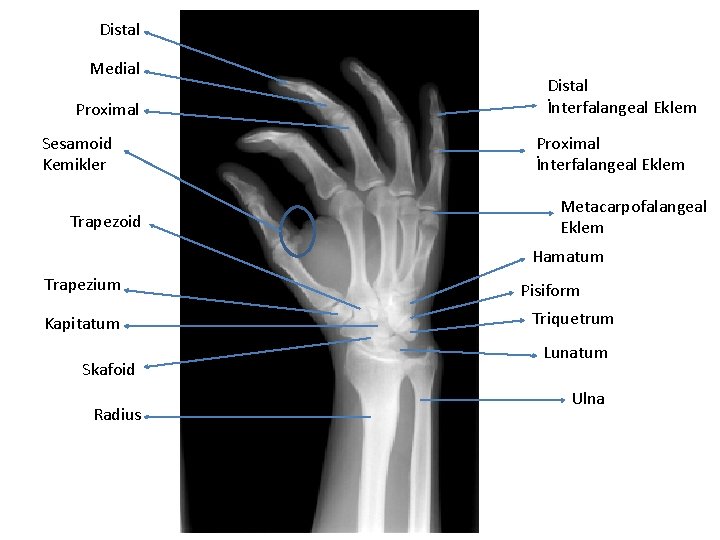

Distal Medial Proximal Sesamoid Kemikler Trapezoid Distal İnterfalangeal Eklem Proximal İnterfalangeal Eklem Metacarpofalangeal Eklem Hamatum Trapezium Kapitatum Skafoid Radius Pisiform Triquetrum Lunatum Ulna